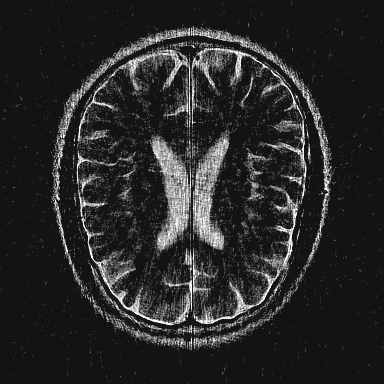

This article presents a novel undersampled magnetic resonance imaging (MRI) technique that leverages the concept of Neural Radiance Field (NeRF). With radial undersampling, the corresponding imaging problem can be reformulated into an image modeling task from sparse-view rendered data; therefore, a high dimensional MR image is obtainable from undersampled $k$-space data by taking advantage of implicit neural representation. A multi-layer perceptron, which is designed to output an image intensity from a spatial coordinate, learns the MR physics-driven rendering relation between given measurement data and desired image. Effective undersampling strategies for high-quality neural representation are investigated. The proposed method serves two benefits: (i) The learning is based fully on single undersampled $k$-space data, not a bunch of measured data and target image sets. It can be used potentially for diagnostic MR imaging, such as fetal MRI, where data acquisition is relatively rare or limited against diversity of clinical images while undersampled reconstruction is highly demanded. (ii) A reconstructed MR image is a scan-specific representation highly adaptive to the given $k$-space measurement. Numerous experiments validate the feasibility and capability of the proposed approach.